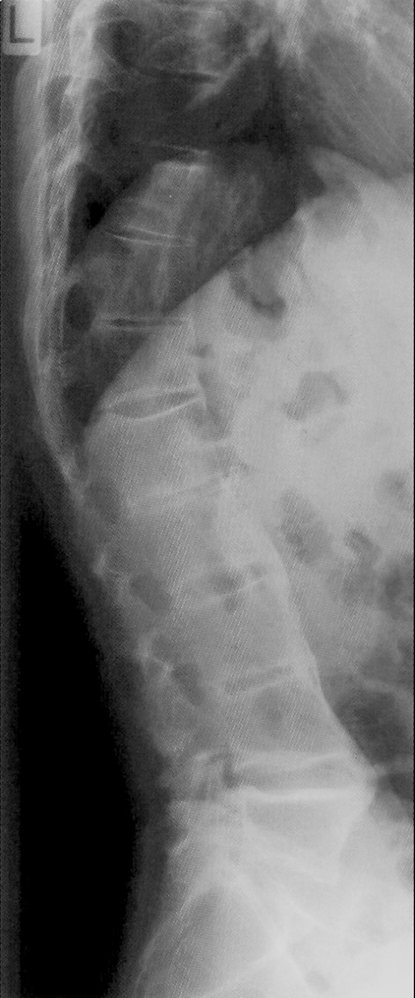

Spine (AP and lateral views)

• Characteristic findings

• Loss of lumbar lordosis: abnormal straightening of the spine

• Ankylosis of costosternal and costovertebral joints

• Dagger sign

• A radiodense line running through the center of vertebral bodies on AP view

• Caused by ossification of vertebral ligaments

• Bamboo spine: seen in later stages and is caused by the following

• Ossification of outer fibers of the annulus fibrosus resulting in ankylosis (fusion) of intervertebral joints

• Syndesmophytesbetween adjacent vertebral bodies (see “Syndesmophytes vs. osteophytes”)

• Shiny corners sign: reactive sclerosis of the superior and inferior margins of vertebrae